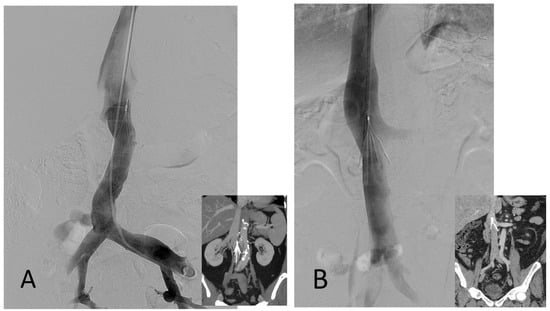

1. Introduction

2.5. Filter Placement

2.6. Filter Retrieval